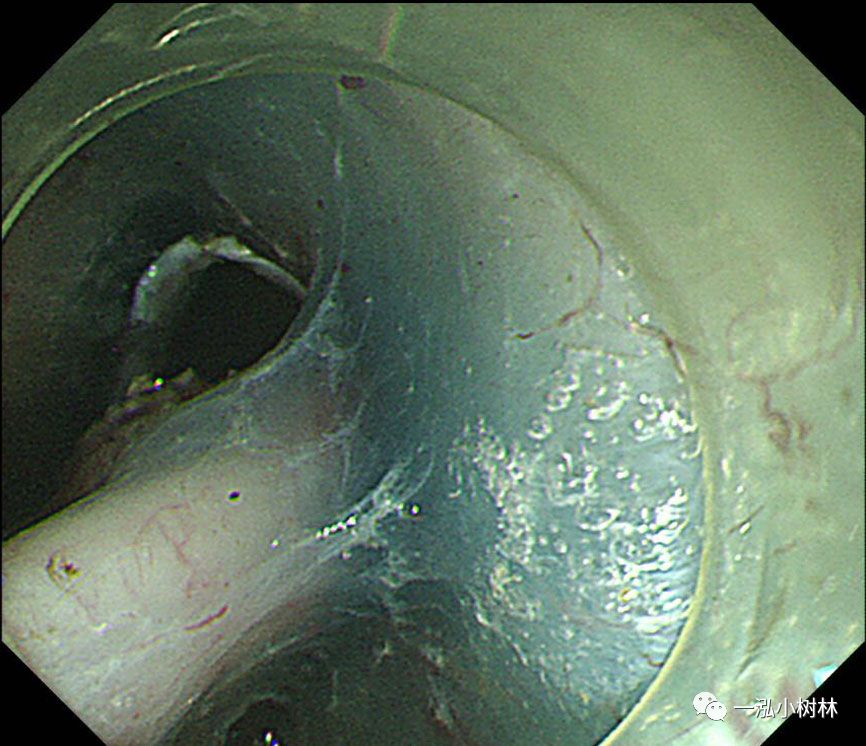

图8 行左侧黏膜下剥离术。在重力的作用下,黏膜剥离(左侧卧位行ESD)

图9 在标本的背面进行钛夹牙线牵引